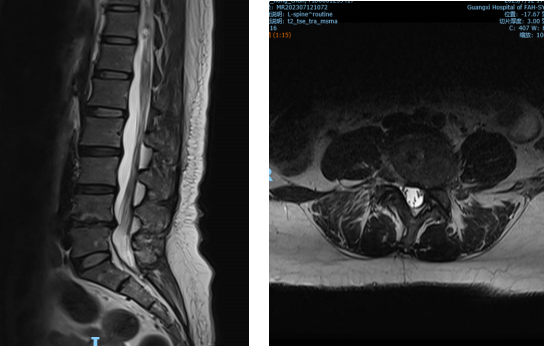

▲②术前MRI片

“医生,我这半年来腰痛的厉害,右腿现在又痛又麻,走路都困难,有什么办法处理吗?”在骨科诊室,患者谭阿姨(化名)苦恼地说道。老虎机app 骨科脊柱外科专业专家欧裕福副主任医师详细询问谭阿姨病史,并为她安排了细致的检查,最终诊断为腰椎管狭窄症+腰椎滑脱症。

结合谭阿姨下腰部明显压痛、右下肢疼痛及活动障碍等症状,骨科脊柱外科团队经过多次术前讨论,并联合麻醉手术中心团队,为谭阿姨制定了个性化的诊疗方案,决定运用经皮内镜下腰椎减压融合技术为患者进行治疗。